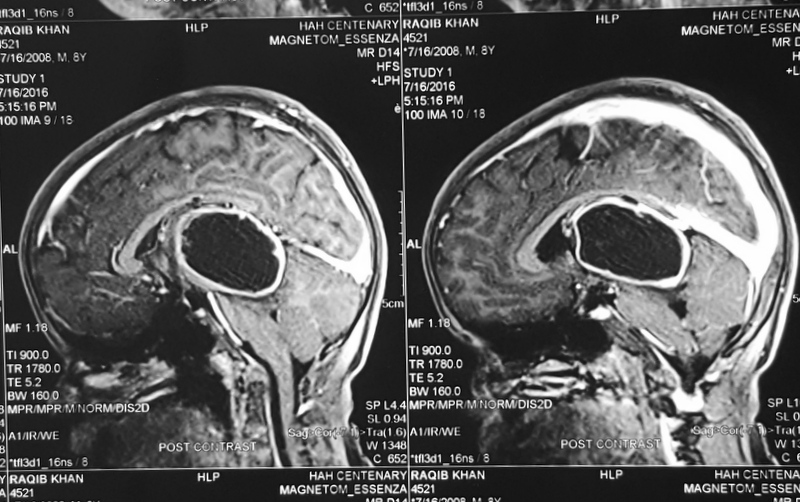

Pilocytic astrocytoma of Posterior Third Ventricle

A 9-year-old male child was evaluated for recurring headaches. Clinically, he had papilloedema. Imaging studies (Figs 1 to 3a & b) showed large posterior third ventricular tumor exhibiting peripheral rim contrast enhancement. The tumour was excised under general anaesthesia, in sitting position, by Supracerebellar Infratentorial approach. The tumour could be excised completely. He has been followed up, and MRI after three years showed only postoperative changes and no tumour residue (Figs 4a & b).

(Fig 4a)

(Fig 4b)